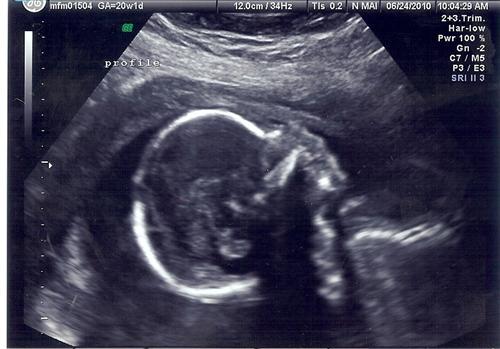

Back from my level 2!!!!!! (with pics)

I would 1st like to thank everyone for their good wishes. Everything is 100% perfect with the baby and it is measuring perfectly from every aspect. Estimated weight is 12ounces so far. They did up my dose of insulin, but are thrilled with how this pregnancy has progressed thus far. The best news is that my cervix has closed!!!

Now here are some pics...

and yes, we caved! It is definitely 100%.......